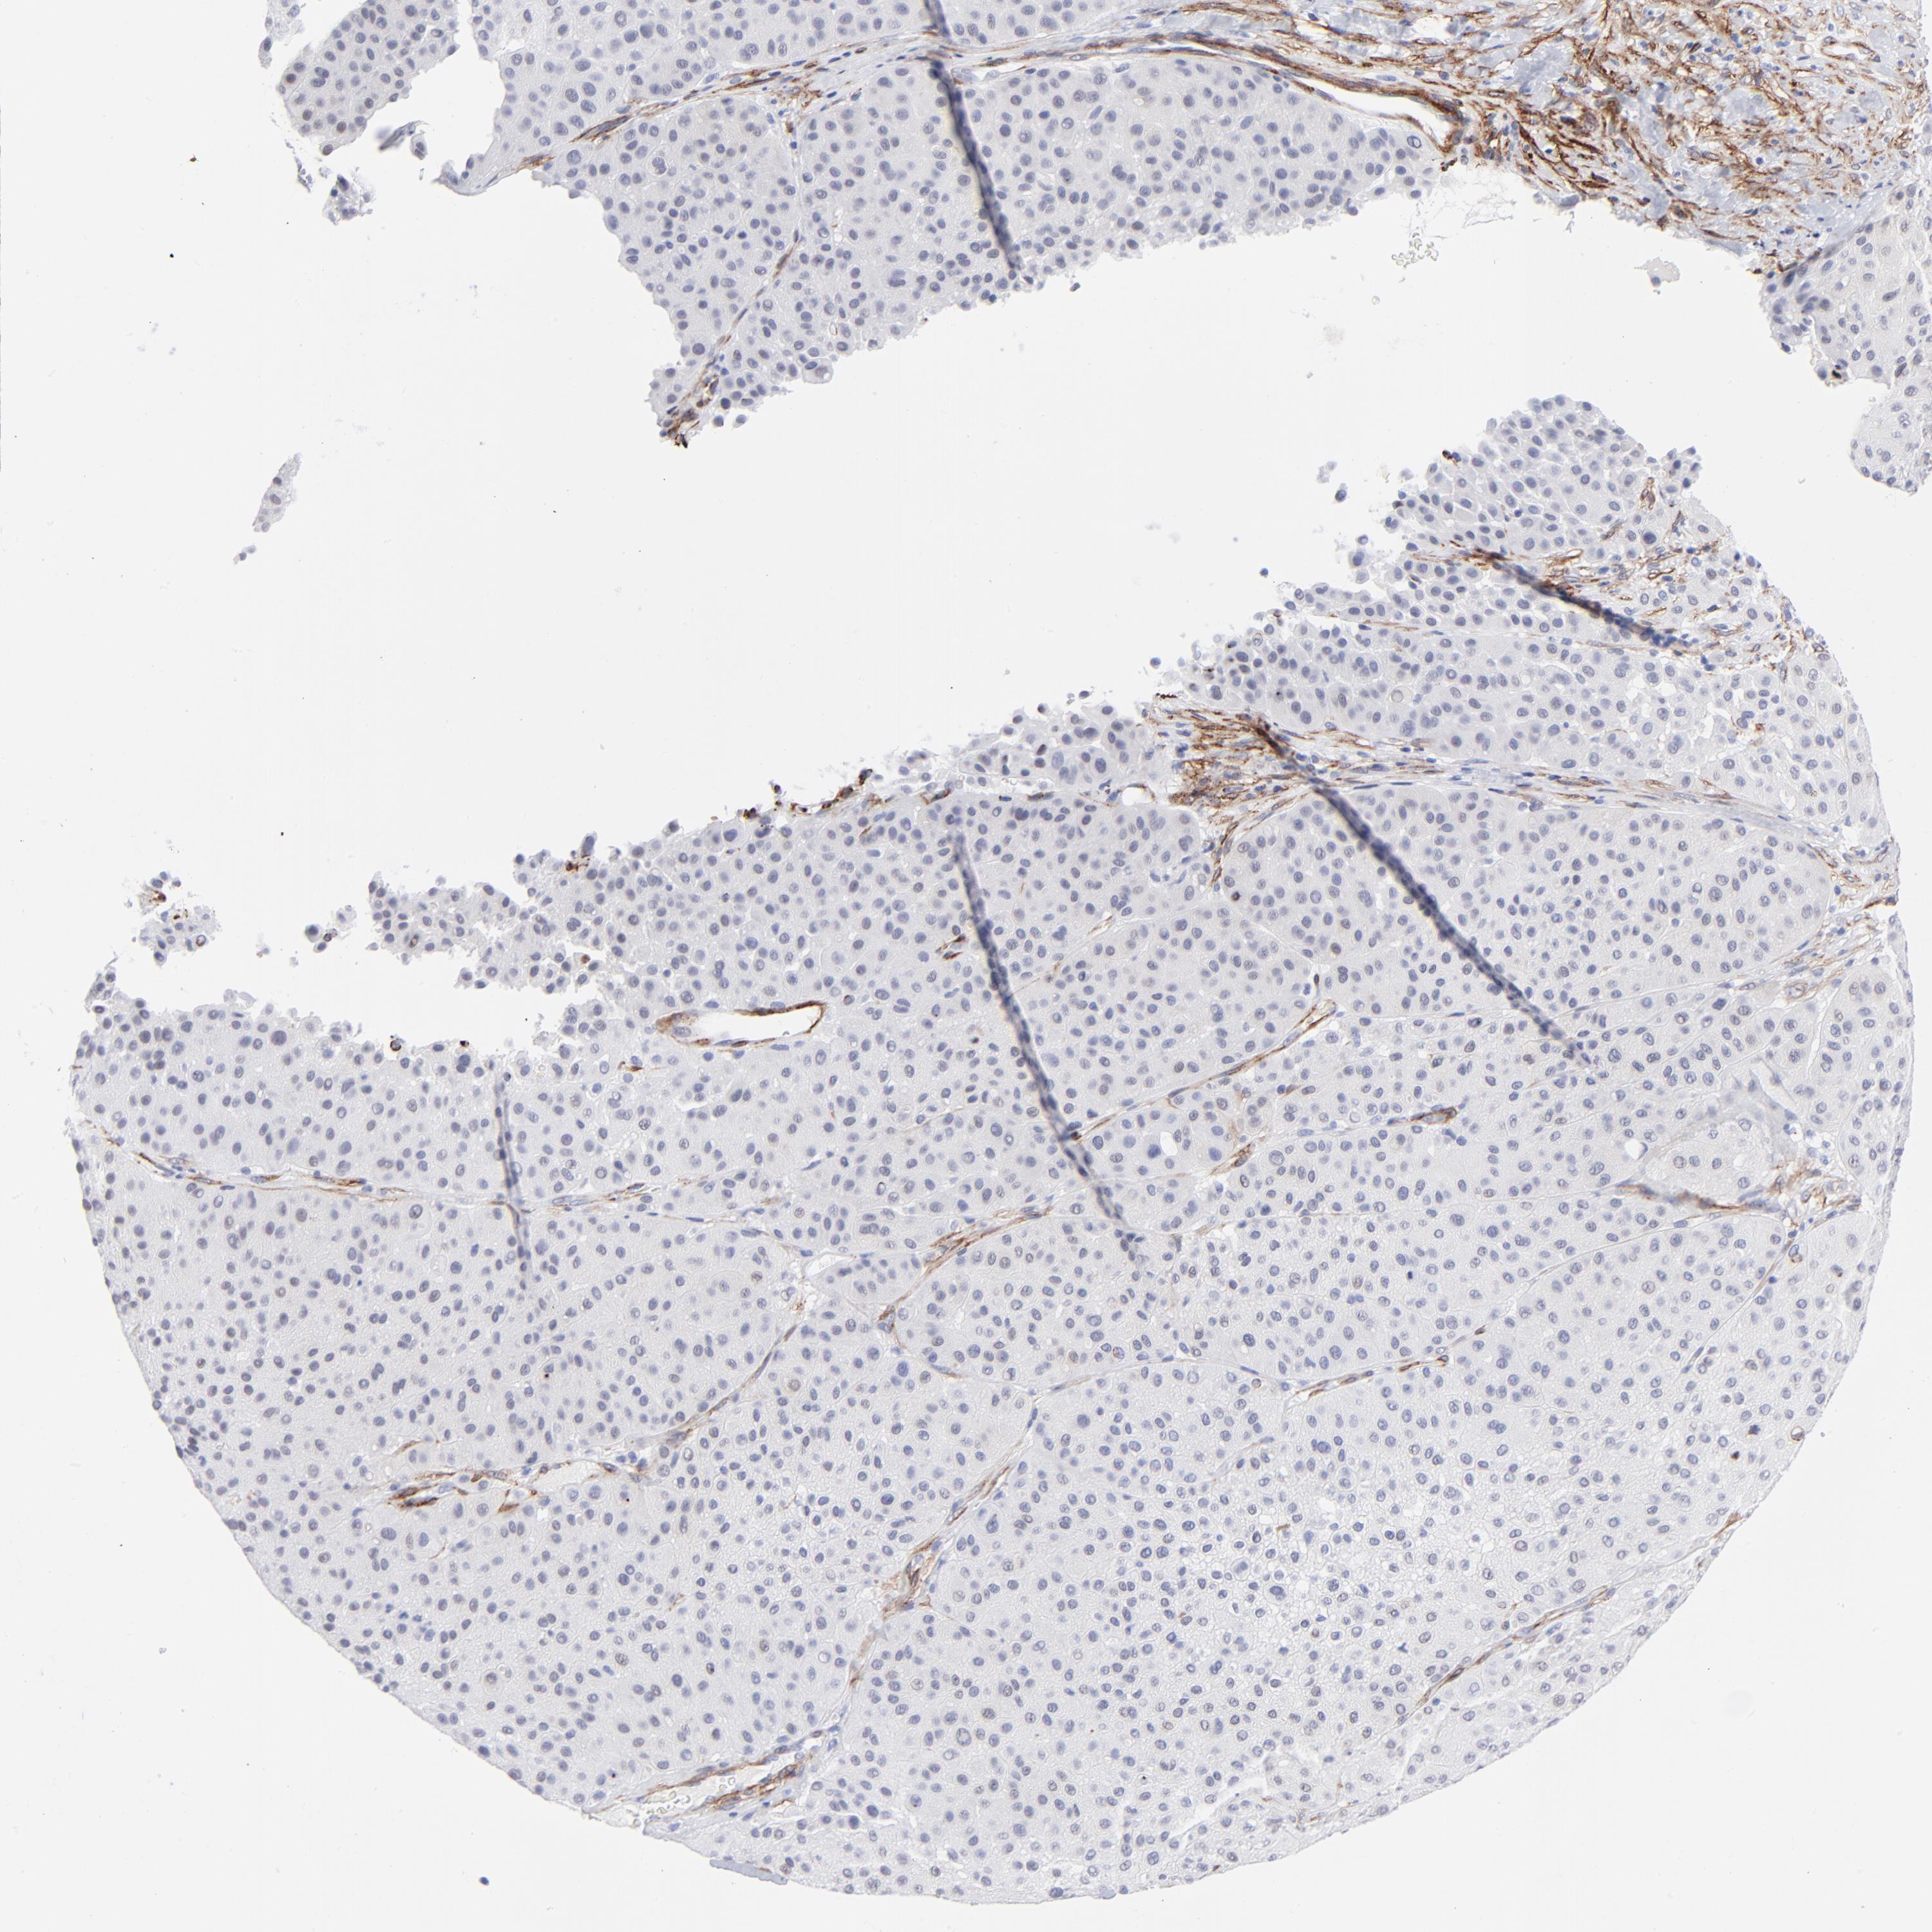

MELANOMA - Protein expressioni

A mouse-over function shows sample information and annotation data. Click on an image to view it in a full screen mode. Samples can be filtered based on level of antibody staining by selecting one or several of the following categories: high, medium, low and not detected. The assay and annotation is described here.

Note that samples used for immunohistochemistry by the Human Protein Atlas do not correspond to samples in the TCGA dataset.

Antibody stainingi

Antibody staining in the annotated cell types in the current human tissue is reported as not detected, low, medium, or high, based on conventional immunohistochemistry profiling in selected tissues. This score is based on the combination of the staining intensity and fraction of stained cells.

Each image is clickable and will lead to virtual microscopy that enables deeper exploration of all samples and also displays staining intensity scores, fraction scores and subcellular localization as well as patient and tissue information for each sample.

Antibody CAB003842

Antibody CAB018144

Staining

High

Medium

Low

Not detected

Intensity

Strong

Moderate

Weak

Negative

Quantity

>75%

75%-25%

<25%

None

Location

Nuclear

Cytoplasmic/membranous

Cytoplasmic/membranous,nuclear

Malignant melanoma, NOS

Malignant melanoma, Metastatic site